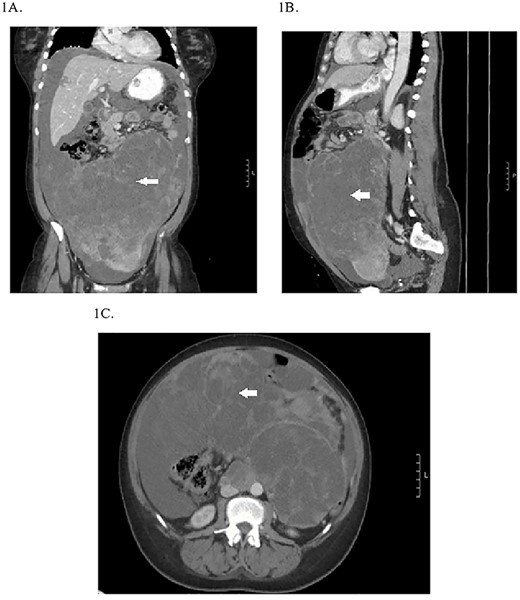

A 49-year-old perimenopausal African American female presented to an outside hospital emergency department (ED) with a 1-month history of intermittent vaginal bleeding, abdominal pain, bloating, constipation and unintentional weight loss. She was found to have a 22-cm pelvic mass on computed tomography (CT) scan, elevated CA-125 and significant anemia requiring blood transfusion and a negative endometrial biopsy. She was scheduled for an elective exploratory laparotomy but re-presented to the ED with worsening abdominal pain, nausea and vomiting prior to her surgery. Repeat CT scan showed interval increase in size of pelvic mass to 27 cm (Fig. 1), abdominal ascites, newly occlusive IVC tumor/thrombus extending into the RA and segmental pulmonary embolism (PE) in the left lower lobe pulmonary artery branches. She was transferred to our hospital for further management given her case complexity.

Preoperative CT abdomen/pelvis showing the pelvic tumor in coronal (A), sagittal (B) and transverse planes (C).